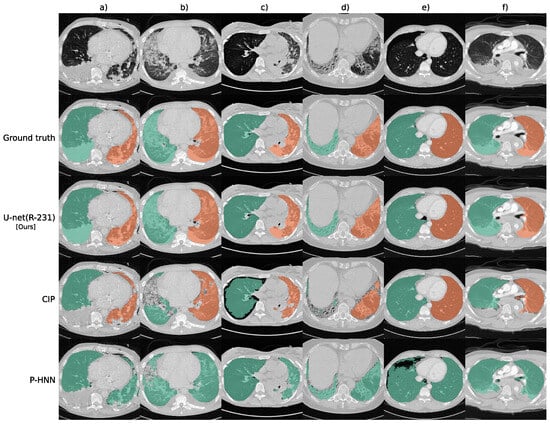

5. Lung Segmentation

- Hofmanninger, J.; Prayer, F.; Pan, J.; Röhrich, S.; Prosch, H.; Langs, G. Automatic lung segmentation in routine imaging is primarily a data diversity problem, not a methodology problem. Eur. Radiol. Exp. 2020, 4, 1–13. [Google Scholar] [CrossRef] [PubMed]

- Hu, Q.; Souza, L.F.d.F.; Holanda, G.B.; Alves, S.S.; Silva, F.H.d.S.; Han, T.; Reboucas Filho, P.P. An effective approach for CT lung segmentation using mask region-based convolutional neural networks. Artif. Intell. Med. 2020, 103, 101792. [Google Scholar] [CrossRef]